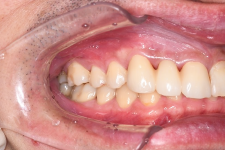

症例7. 結合組織移植

| 術前 | 術後 |

![]() |

抜歯後、骨吸収が顕著にみられ、審美障害を起こしている。

歯肉をパウチ状に剥離

上顎口蓋側から移植片を採取

パウチ状にした部分に入れ込む

軟組織の増大

審美性の改善